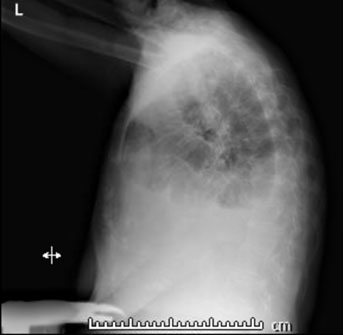

She stated that her shortness of breath was exacerbated by exertion and associated with orthopnea, paroxysmal nocturnal dyspnea, and swelling in her lower extremities. She denied any recent history of trauma, symptoms of respiratory infection, and had not had any recent surgery. After a chest X-ray was completed and demonstrated a small left and moderate right pleural effusion (Figure 1 and Figure 2), she was given a trial of furosemide. Five days later, she returned to the Cancer Center stating that her symptoms had not improved. At that time, she was noted to have a SpO2 of 85% on room air and rales in the bilateral lower lung fields. She was immediately referred to the hospital for admission.

Figure 1: Chest X-ray in PA view demonstrating small left and moderate right pleural effusions.

Figure 2: Chest X-ray in lateral view demonstrating small left and moderate right pleural effusions.